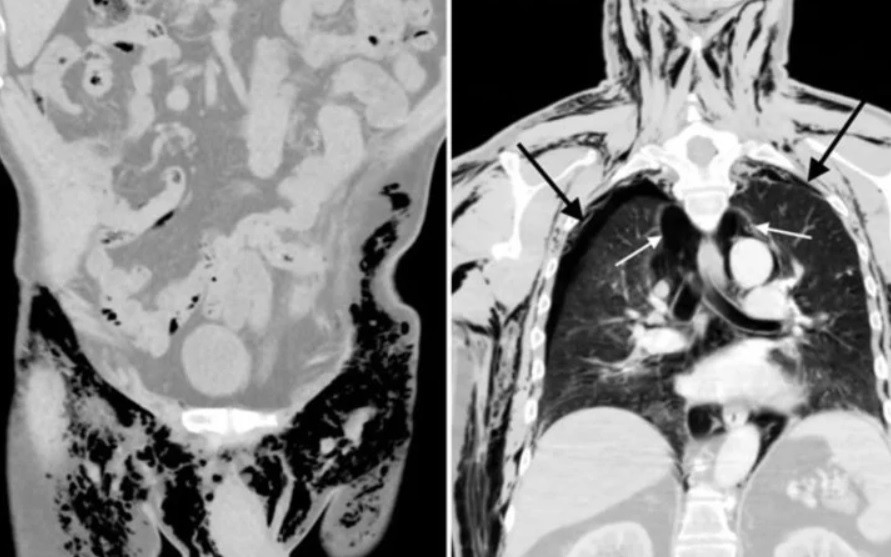

Los análisis al paciente arrojaron también un neumotórax bilateral, una acumulación de aire en una cavidad entre los pulmones y el tórax conocida como cavidad pleural.

Asimismo, le detectaron neumomediastino, que se debe también a una acumulación del aire, esta vez en una cavidad ubicada entre los dos pulmones.

Y, por último, le diagnosticaron un enfisema subcutáneo a raíz de la penetración de aire en los tejidos ubicados bajo la piel.